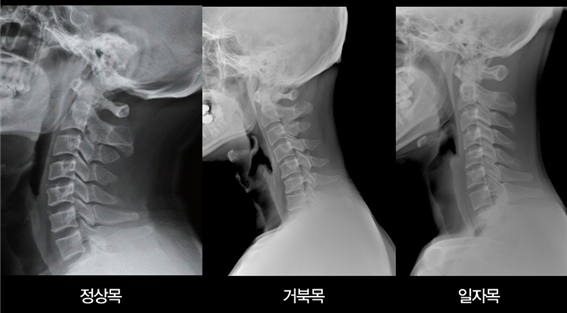

1. 경추 통증의 원인 경추 통증은 주로 목 주변의 근육, 인대의 긴장 또는 염증에서 비롯됩니다. 가장 흔한 원인은 목을 앞으로 빼는 자세를 하거나, 고개를 숙인 채 스마트폰을 장시간 사용하거나, 장시간 고정된 자세로 컴퓨터 작업을 하는 것과 같은 잘못된 자세입니다. 이러한 습관은 경추의 하중을 증가시키고 근육뭉침이나 거북목, 일자목 등의 구조적 변화를 일으켜 통증을 유발할 수 있습니다. 2. 경추통증을 유발하는 질환 1) 거북목, 일자목 정상 경추는 C자형 곡선을 가지고 있어 머리의 무게를 지탱하고 외부의 충격을 흡수 및 완화하는 역할을 합니다. 그러나 잘못된 자세가 지속되면 경추의 곡선이 무너지고 경추가 수직에 가까워지며, 목과 어깨에 무리가 가게 됩니다. 대표적인 증상으로는 목 뒤가 자주 뻐근하고, 어깨와 등이 굽어있거나, 두통 혹은 어깨 결림이 발생하거나, 쉽게 피로해지고 집중력이 저하되는 증상 등이 있습니다. 거북목이나 일자목으로 인한 증상 대부분은 근육통이 동반한 것으로 자세 교정처럼 간단한 치료만으로도 개선이 가능합니다. 2) 경추 추간판 탈출증(목디스크) 경추 추간판 탈출증은 목 주변의 근육과 인대가 오랜 시간 압력을 받아 퇴행되면서 디스크가 탈출하거나 돌출되어 통증을 유발하는 퇴행성 척추질환입니다. 대표적인 증상으로는 목 주변의 뻐근함과 경추통증, 어깨통증 등이 느껴질 수 있습니다. 한쪽 팔의 저림, 통증, 감각 이상이 나타나거나 손의 힘 약화, 세밀한 동작이 어려워지는 증상도 나타날 수 있으며, 특히 상부경추 손상 시 경추통증을, 하부경추는 팔저림을 일으킵니다. 단순히 경추통증만 있다면 경추 추간판 탈출증라고 단정짓기 어렵지만, 이 외에도 팔과 손이 저리고 원인 모를 두통이 동반 될 경우 정밀 검사가 필요합니다. 3) 후종인대 골화증 후종인대 골화증은 척추체 뒤쪽을 위아래로 연결하는 인대 중 하나인 후종인대가 비정상적으로 단단해지는 질환입니다. 정상적으로 움직일 수 있도록 도와야 할 인대가 딱딱하게 골화되면서 척추관을 지나는 척추 신경을 압박하게 되고, 이 때문에 신경 장애를 발생시킵니다. 주로 손에 감각 이상이 나타나거나 팔 또는 목 부위에 찌릿찌릿한 통증이 나타납니다. 또한, 인대가 척수를 압박하고 있어 보행장애가 동반될 가능성이 있고, 심할 경우 배변 및 배뇨 장애가 발생할 수 있으므로 각별히 주의해야 합니다. 4) 척수증 척수증은 뇌에서부터 목을 통해 전신으로 퍼지는 중추신경인 척수가 디스크, 협착증 등 여러 원인에 의해 물리적으로 압박되어 손상이 생긴 질환입니다. 척수증이 있는 경우, 경추 MRI 검사 시 척수가 하얗게 변한 시그널이 보이는 게 일반적이기 때문에 MRI 검사를 통해 척수증을 진단하고 있습니다. 다만, 증상 초기에는 경추통증을 비롯해 어깨, 손, 팔 등에서 통증과 저림 등의 증상이 나타나기 때문에 목디스크로 착각하는 경우가 많습니다. 만약 아무런 치료도 받지 않은 채 척수증을 그대로 방치한다면, 신경이 지속적으로 손상되어 보행장애나 일상생활이 불가능한 정도의 마비, 더 심한 경우에는 사지마비까지 이어질 수 있습니다. 따라서 척수증은 치료를 통해 더 이상의 추가적인 진행을 막고, 근력이나 감각기능 등을 회복하도록 해야 합니다. 5) 경추관 협착증 경추관 협착증은 경추(목)을 둘러싸고 있는 목의 근육과 인대의 퇴행 또는 골극 형성, 디스크의 퇴행 등으로 인해 경추관이 좁아지며 신경을 압박해 통증이 발생하는 질환입니다. 주로 40~50대 이상의 중장년층에서 발생하는 대표적인 퇴행성 질환 중 하나지만, 선천적으로 척추관이 좁은 경우 또는 외상성 손상의 결과로 인해 나타나기도 합니다. 3. 경추질환의 치료 방법 비수술적 치료가 우선으로 시행됩니다. 약물치료, 물리치료, 견인치료 등의 보존적 치료를 시행하며 증상의 완화를 관찰해야 합니다. 또한 통증을 유발하는 신경에 주사를 통해 직접 약을 주입하는 신경차단술과 같은 주사요법도 시행할 수 있습니다. 대부분의 경추 질환은 초기엔 비수술적 치료로 호전 가능합니다. 6주 이상 비수술적 치료에도 호전이 없는 경우, 팔/다리 감각 저하, 보행/배변 장애 진행 등의 상황에서는 환자 상태와 영상검사 소견에 따라 수술적 치료를 고려해야 합니다. 4. 경추질환의 예방과 자가관리법 - 자세 교정 : 스마트폰은 눈높이, 모니터는 정면 - 스트레칭 : 30분마다 목돌리기, 어깨 회전 운동 같은 스트레칭 시행 - 숙면 자세 주의 : 경추 곡선을 지지할 수 있는 베개 사용 - 1주 이상 통증이 지속되거나 저림/마비 증상이 발생하면 즉시 신경외과 진료가 필요합니다. |